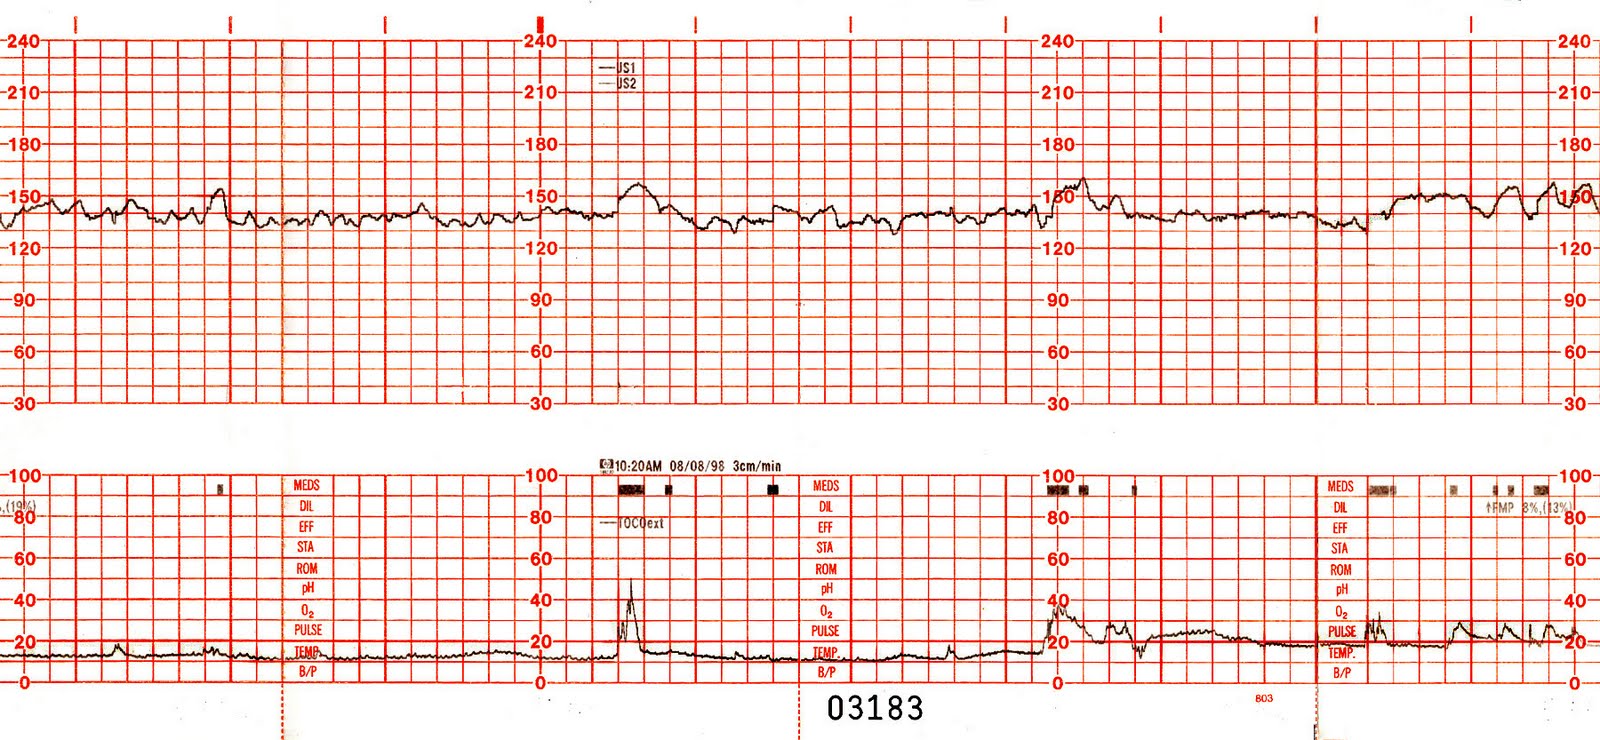

Bu testte anne karnının üzerine bir kemer atılır ve bu kemere 2 adet cihaz bağlanır. Bağlanan bu cihazlar anne karnındaki bebeğin kalp atım hızı ile rahim kasılmalarını incelemek içindir. Bu cihazlar anne karnına kemer ile sabitlendikten sonra anne karnındaki bebeğin hareketlerini işaretlemek için yardımcı olmalıdır. Yani bebek her hareket ettiğinde anne de bunu saptamak için düğmeye basar. NST testinin ortalama süresi 20 ila 30 dakika arasındadır. Bu testin olumlu bir şekilde sonuçlanması için anne karnındaki bebeğin kalp atım hızı düzgün bir şekilde gözlemlenebilmelidir.

Bu durumu açıklamak için şöyle diyebiliriz, anne karnındaki bebek en az 20 dakika olan gözlem süresinde 2 defa ve 10 saniye süren kalp hızlanmasını belli etmelidir. Bu süre zarfında bebekte en az 2 defa kalp atış hızı saptanırsa bu testin daha uzun bir süre yapılmasına gerek yoktur. Bu durum anlatıldığı gibi oluşur ise bebeğin anne karnında güvende olacağı en az 1 hafta boyunca kesinleşmiş olur.

Bu testte bakılan, bebeğin anne karnında hareket ettiği kalp atım hızının bu hareketlere verdiği tepkidir. Anne karnında sağlıklı olan bir bebek hareket ettiğinde buna bağlı olarak da kalp atım hızı hızlanır ve hareket etmediği zamanda kalp atım hızı yavaşlar. Bu testin altında yatan ana fikir ise bebeğin anne karnında sağlıklı bir şekilde barınması ve hareket etmesi ile bebekteki kalp atım hızının normal olması için anne karnında yeteri kadar oksijen olması gerektiğidir. Anne karnında yeteri kadar oksijen yok ise ne bebeğin hareketleri ne de bebek kalp atım hızı istenilen normallikte olmaz. Oksijen seviyesinin düşmesi de genelde plasenta da bir sorun olduğuna işarettir.

Pozitif yani olumlu olan test sonucu başka bir değiş ile ‘’Reaktif NTS’’ bebek anne karnında hareket ettikçe kalp atım hızı da buna bağlı olarak hızlanıyor demektir. Olumsuz sonuç ise diğer adı ile ‘’Non-reaktif NTS’’ bebeğin anne karnındaki hareketleri doğrultusunda kalp atım hızında herhangi bir artış gözlemlenememesi durumudur. Böyle bir durumda anne karnında olan bebeğin yeterli derecede oksijen alamadığı ön görülür ve hem anne hem de bebek sağlığı için daha ileri düzeyde testler yapılır.